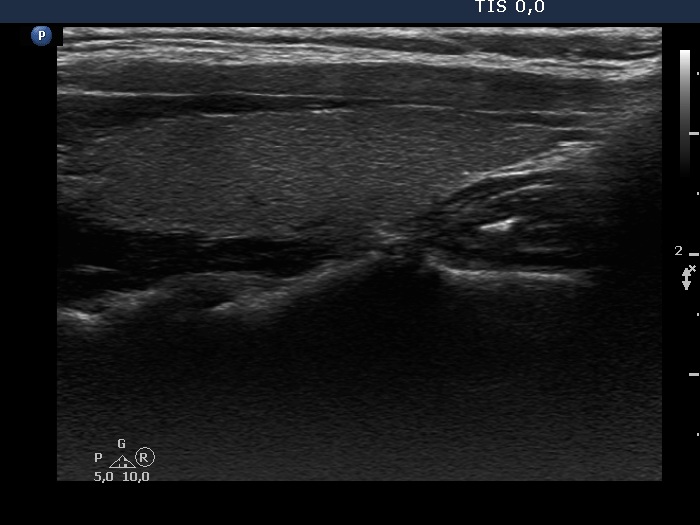

Consecutive patients with the final diagnosis of Hashimoto's thyroiditis - case 45 (1024) (ultrasonographic picture 5)

Left lobe, longitudinal view.